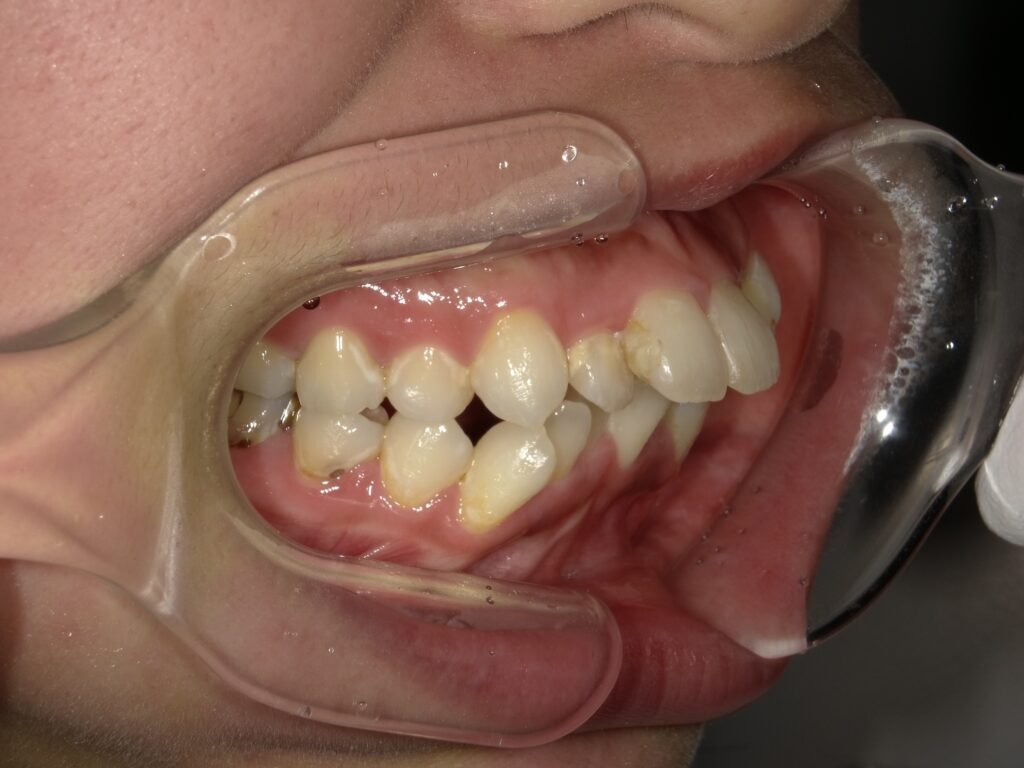

① 叢生(そうせい)=ガタガタの歯並び

歯が重なっていたり、八重歯が飛び出していたりする状態です。

アジア人は顎が小さいため、歯がきれいに並びきらないことが多いんです。

日本では「八重歯=かわいい」なんて文化もありましたよね。